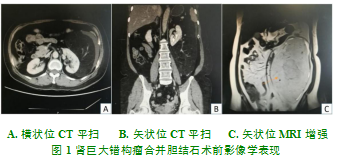

实验室检查:生化实验中血浆总蛋白↑87g/L,直接胆红素↑7.4umol/L,总胆红素↑21.6umol/L,葡萄糖↑6.6mmol/L;血常规及肝功能检查均正常。胸片和心电图等均正常。外院腹部B超示:胆囊壁3mm,毛糙,囊内充满密集点状及斑片状强回声,较长处达5mm;同时在胆囊颈部可见15mm的强回声并伴有声影。行上腹部CT平扫提示(见图1):胆囊大小正常,囊腔密度增高,颈部呈圆形高密度阴影,直径约为2.2cm;左侧腹腔见一巨大占位(病灶未包全),病灶边界清晰,以脂肪成分为主,其内见斑片状絮状模糊影,并见较多血管包绕、穿行,周围肠管呈受挤压推移改变,余未见异常。进一步行上腹部MRI平扫增强提示(见图1):肝内外胆管未见扩张;胆囊壁轻度增厚,底部可见较低信号,呈点状分布;右肾见直径约0.7cm长T1长T2信号影,边界清晰;左侧后腹膜区见大小约25cm×15cm×13cm巨大肿块影;呈高信号影,内部可见纤维分隔及血管影,其中供血血管来源于左肾动脉,脂肪抑制相呈低信号,肿块周围见少量液体信号影,余未见异常。盆部CT平扫+增强检查(见图1):左侧腹部脾脏与左肾之间见约24cm×17cm×11cm的占位影,CT值为-52HU;增强后,见血管强化与部分间隔和包膜强化,推移脾脏及左肾。为进一步了解肿瘤血供情况,行双肾动脉CTA示:左边肾周见一大小约24cm×17cm×11cm脂肪密度块状影,边界清晰,CT值约-71HU;团块内密度不均匀,可见片絮状稍高密度及多发血管影,肿瘤供血血管来源于左肾动脉,邻近组织受压移位改变;右侧肾周正常;余双肾肾动脉及主要分支正常。临床诊断:胆囊结石伴慢性胆囊炎合并原发性左肾巨大错构瘤。